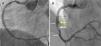

A 45-year-old man with previous history of hyperlipidemia was admitted with an inferior myocardial infarction requiring implantation of a drug-eluting stent (DES) in the mid right coronary artery. One year later he presented with angina and angiography demonstrated severe in-stent restenosis (ISR). After lesion predilation with a cutting balloon, a 3.5 mm×18 mm bioresorbable vascular scaffold (BVS) (Absorb, Abbott Vascular, CA) was implanted and postdilated up to 24 atm using a non-compliant balloon, with an excellent final result (Figure 1A). Optical coherence tomography (OCT) confirmed appropriate expansion and apposition of the BVS, with a minor intimal dissection at its proximal edge. The patient remained completely asymptomatic, but at nine months underwent a scheduled angiography that revealed moderate ISR of the BVS. In addition, a coronary artery aneurysm (CAA) was detected immediately proximal to the BVS location (Figure 1B). OCT showed the presence of an heterogeneous pattern of neointimal hyperplasia (Figure 2A and B) and confirmed the origin of the CAA immediately proximal to the BVS edge (Figure 2C and D). Interestingly, a minor rupture with intraluminal thrombus was also detected at the origin of the CAA. As fractional flow reserve was 0.79 and instantaneous wave-free ratio was 0.93, and the patient denied any symptoms, the lesion was not treated. During follow-up, a stress echocardiogram was negative.

(A and B) Angiographic result after implantation of a bioresorbable vascular scaffold (BVS) in the proximal left anterior descending coronary artery (small white arrows indicate the ends of the BVS); (C and D) at nine-month follow-up formation of a coronary artery aneurysm (yellow arrow) is demonstrated in the mid segment of the BVS.